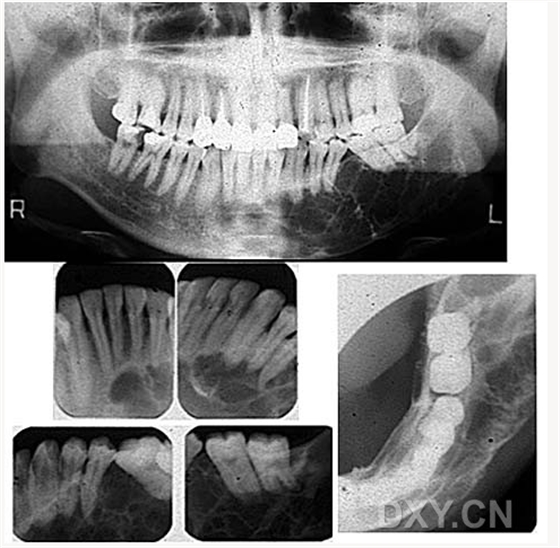

成釉細(xì)胞瘤

鼻鄂囊腫

根尖囊腫

骨肉瘤

涎石病

頜骨纖維性結(jié)構(gòu)不良癥

球狀上頜囊腫

含牙囊腫

球狀上頜囊腫    含牙囊腫

骨髓炎

頜骨骨折

牙源性鈣化囊腫

牙瘤!

牙源性鈣化囊腫    牙瘤!

牙瘤